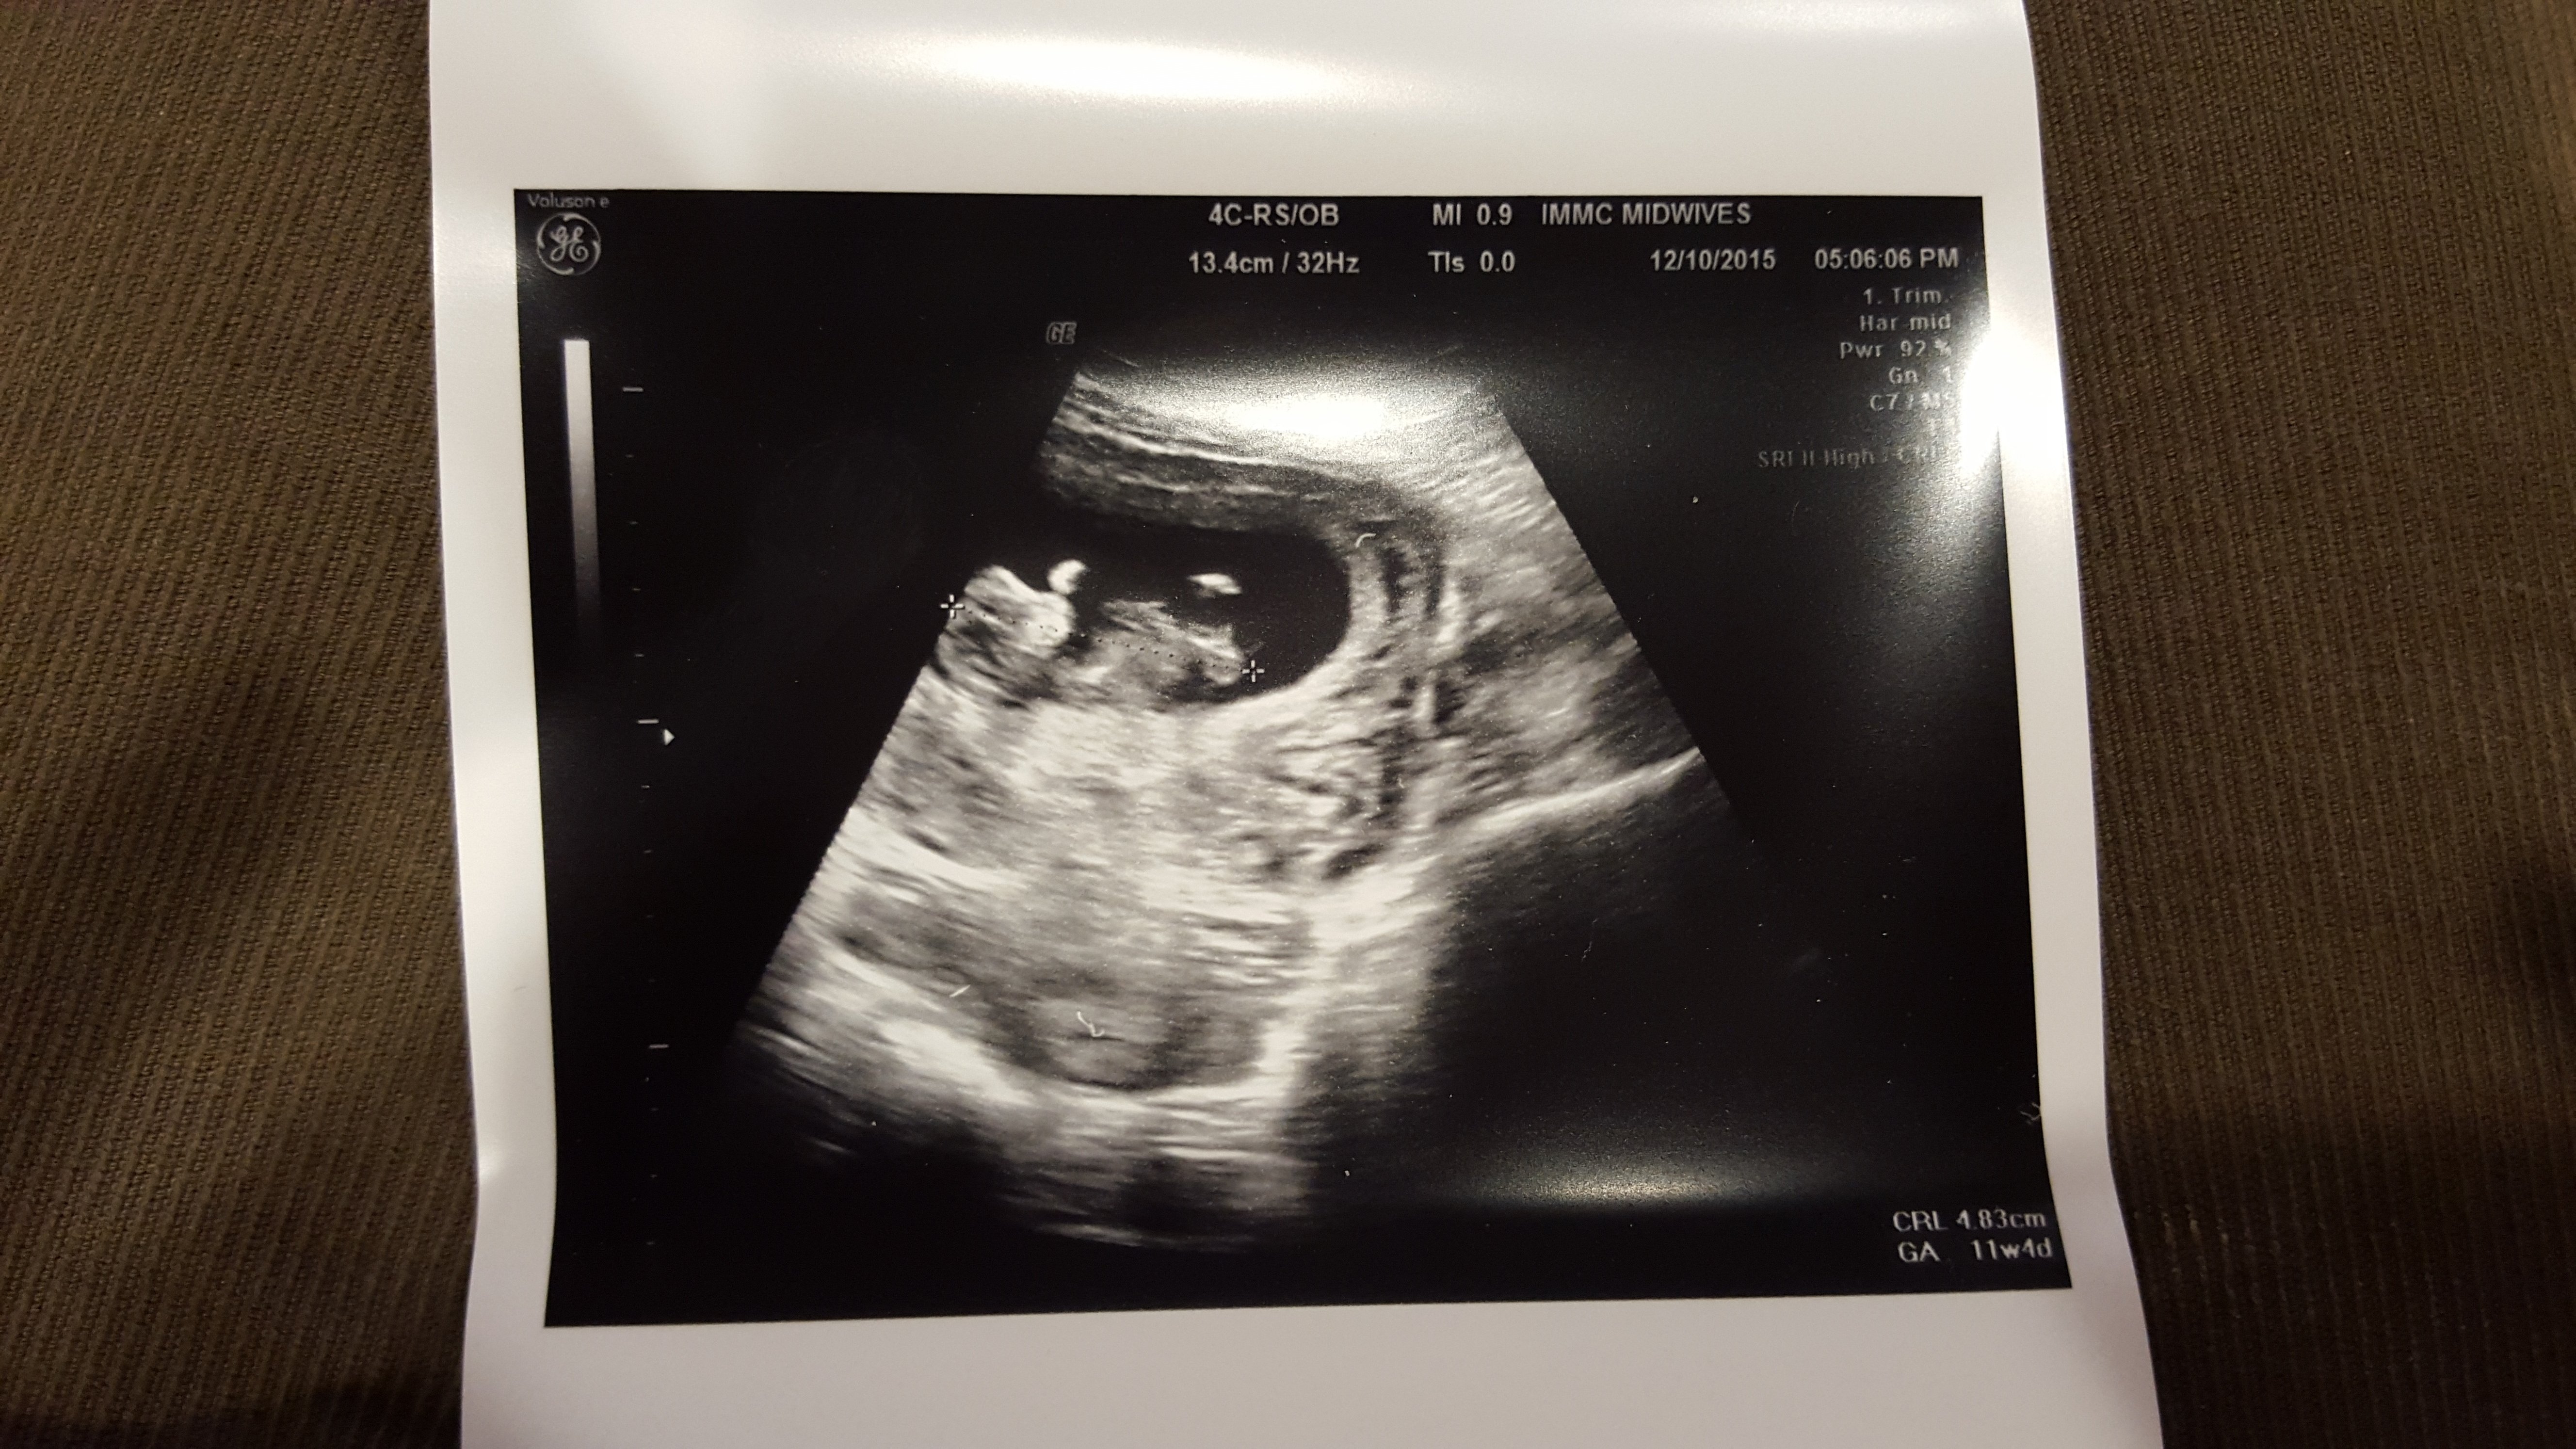

My midwife is so awesome!! After our initial appointment today she pulled out the ultrasound machine so we could have a quick look at our peanut. This baby is super active, would barely hold still long enough for a picture. Our midwife enjoyed it as much as we did. I am measuring 2 days ahead at 11 weeks 4 days, but not enough to move up my due date.